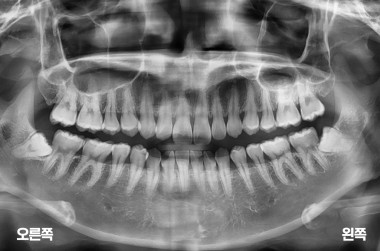

4개의 사랑니 발치

MORE